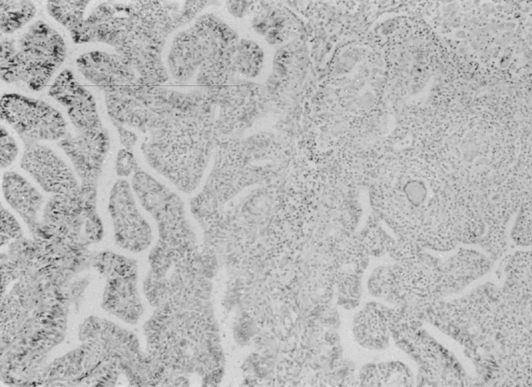

Microscopically, granulomata and a chronic inflammatory infiltrate may involve the full thickness of the tubal wall, and caseation necrosis is common in advanced states. Some tubercles have a caseous center, which, as they progress, involves the overlying mucous membrane or causes pressure atrophy. After liquefaction, the caseous foci pour their bacilli into the lumen and form an ulcer at the site. Caseation or a pyogenic membrane lines the ulcer; beyond the inner zone is an area of vascular granulation tissue containing epithelioid and giant cells. Adhesion of the individual foci may occur, resulting in large cystic spaces—pseudofollicular salpingitis. When healing occurs, the picture is further changed, and calcium deposits, hyalinization, and increased fibrous tissue may be seen. The mucosa frequently exhibits a hyperplastic, adenomatous pattern with a complex network of fused papillae that may be confused with adenocarcinoma (Fig. 2) and has been associated with ectopic pregnancies.37,44 There is some suggestion that this pattern may actually predispose to the development of tubal adenocarcinoma, although the evidence is insufficient for statistical assessment.45 Tuberculous salpingitis may contain Schaumann bodies, which are conchoidal, laminated, calcified structures surrounded by foreign body giant cells (Fig. 3). In chronic tuberculous salpingitis, unless multiple sections are taken, the characteristic lesion may be missed.

Fig. 2. Tuberculous salpingitis. Chronic salpingitis due to tuberculosis presents the characteristic histologic features of the tuberculous granuloma: lymphocytes, epithelioid cell granulomata, and giant cells of both the Langerhans and the foreign body type are seen. Tuberculous infection of the fallopian tube often results in an “adenomatous” proliferation of the lining epithelium. This is seen on the left of this photomicrograph and may give rise to confusion with adenocarcinoma.(×100.)